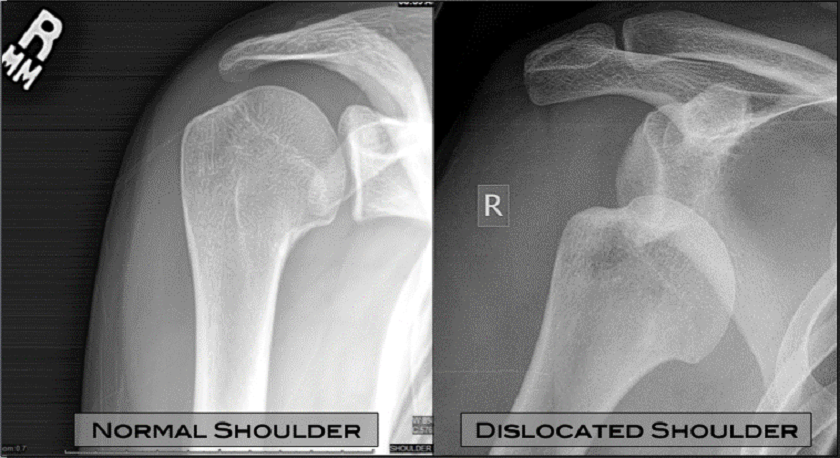

The shoulder joint is considered the most unstable joint in the human body and traumatic anterior dislocation occurs when force is applied to the area, causing the humeral bone to be removed from the socket.